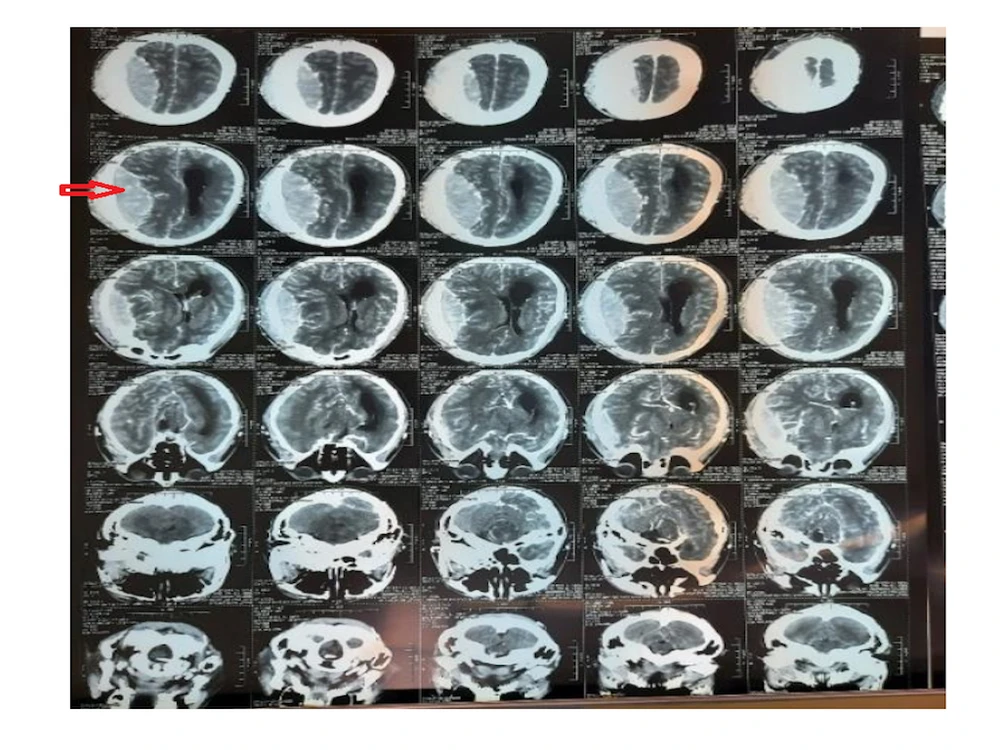

Hình ảnh CT Scan sọ não cho thấy khối bất thường chèn ép nhu mô não, phù não nặng. Sau đó bệnh nhân rơi vào hôn mê, đồng tử bên phải bắt đầu giãn so với bên trái, được đặt nội khí quản, tri giác xấu hơn, yếu nửa người bên trái.

Hình ảnh não trước và sau phẫu thuật. Ảnh: BVCC 1 Hình ảnh não trước và sau phẫu thuật. Ảnh: BVCC 2

Hình ảnh não trước và sau phẫu thuật. Ảnh: BVCC

Để có chẩn đoán chính xác hơn, các bác sĩ đã tiến hành chụp CT Scan sọ não có cản quang cấp cứu kết quả cho thấy có u màng não bán cầu (P) kích thước 10 × 9 × 4cm, khối u gây tăng sinh xương, cơ thái dương và nhiều mạch máu, chèn ép nhu mô não, phù não nặng. Ngay lập tức bệnh nhân được chỉ định phẫu thuật cấp cứu với phương pháp mở sọ và vi phẫu lấy trọn u.